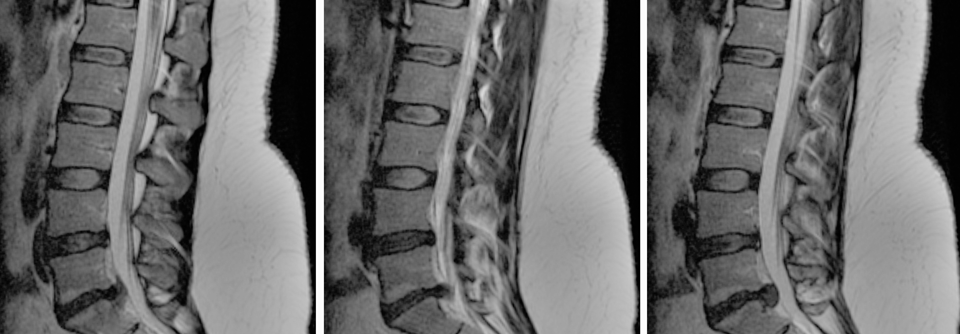

Als wichtige Ursache der Beschwerden gilt die Rückbildung der Tiefenmuskulatur. An der daraus resultierenden Instabilität scheitert dann auch die Krankengymnastik. Genau daran setzt nun eine neue Behandlungsmethode an: ein implantierbarer neuromuskulärer Stimulator. Er regt die betroffene Muskulatur über minimale elektrische Impulse an. Innerhalb weniger Wochen wird die neuromuskuläre Ansteuerung reaktiviert. So kommt es zu einer zügigen segmentalen Stabilisierung der Wirbelsäule.

Einer der ersten Orthopäden, die das System hierzulande verwenden, ist Dr. Jan Schilling von der Abteilung für Wirbelsäulen- und Neurochirurgie am Krankenhaus Tabea in Hamburg. Infrage kommen Patienten mit chronischen unspezifischen Rückenschmerzen ohne Indikation zu OP oder spinal cord stimulation nach erfolgloser konservativer Therapie. Bei dem minimalinvasiven Eingriff platziert Dr. Schilling zwei Elektroden an den Querfortsätzen der LWS, die den Ramus dorsalis der Spinalnerven stimulieren. Über Koinnervation erreichen die Impulse die Tiefenmuskulatur der angrenzenden Wirbel. Die zugehörige Batterie mit Impulsgeber findet s.c. im Gesäß ihren Platz.

Die OP birgt kaum spezielle Risiken. „Wir arbeiten ja nicht epidural, sondern nur im Muskelbereich“, erklärt der Kollege. Zu den Kontraindikationen gehören Voroperationen oder Deformitäten im LWS-Bereich sowie ein liegender Herzschrittmacher oder psychiatrische Krankheiten.